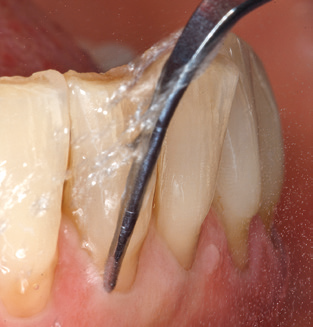

Die gute Ausleuchtung des Arbeitsfeldes stellt eine wesentliche Erleichterung dar. Bei dem von den Autoren genutzten System ist dies gelungen, indem ein 5facher LEDRing in das Handstück integriert wurde. Natürlich werden für dieses System unterschiedliche Arbeitsspitzen für die jeweiligen Indikationsbereiche angeboten. Eine gerade, universell einsetzbare Spitze ist das Basisinstrument zur maschinellen Instrumentierung natürlicher Zähne (Abb. 5a und b). Für schwer zugängliche Bereiche im Seitenzahnbereich werden gebogene Spitzen angeboten, die auch einen Zugang zu freiliegenden Furkationen ermöglichen (Abb. 6).

Nach der maschinellen Reinigung der Zahn und Implantatoberflächen erfolgt eine manuelle Instrumentierung der natürlichen Zahnoberflächen mit konventionellen Handinstrumenten. Bei der manuellen Reinigung ist insbesondere auf einen korrekten Anstellwinkel, eine ausreichende Schärfe, eine gute Abstützung und auf eine von apikal nach koronal gerichtete Arbeitsweise der Kürette zu achten. Zur Nachinstrumentierung der Implantatkonstruktionen sollten entweder Titan oder Carbonküretten verwendet werden (Abb. 8). Ergänzend zum Einsatz von Ultraschallgeräten können in der Erhaltungstherapie auch Pulverstrahlgeräte genutzt werden. Dabei ist jedoch zu berücksichtigen, dass diese Verfahren nicht zum Entfernen harter Beläge geeignet sind und daher die Verwendung von Hand oder Ultraschallinstrumenten nicht komplett ersetzen können. Abschließend erfolgt in jedem Fall eine mechanische Politur der zugänglichen Zahn und Implantatoberflächen mit Polierkelchen und Polierpasten (Abb. 9).